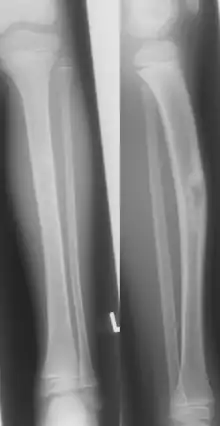

| Jaffe-Campanacci-Syndrome, boy 7 Y, tibial bowing and cortical/subcortial mixed sclerosis | |

Jaffe–Campanacci syndrome is one of the disorders associated with café au lait macules (CALMs). Presentations may include intellectual disability, disseminated non-ossifying fibromas of the long bones and jaw, hypogonadism or cryptorchidism, or giant cell granulomas of the jaw.[2]